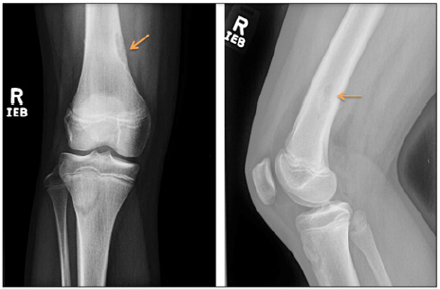

A 12 year old female patient presented to the clinic for right knee pain. She was a cross country runner and had been training for a competition. The patient described waking up in the morning to vague knee pain just above the patella and has been walking with a limp for several days. Ibuprofen has not completely controlled the pain. On exam, there was pain with weight-bearing and tenderness to palpation of the distal femur but no significantly increased pain on range of motion testing. The patient was initially sent home with conservative management. However, the patient returned with worsening pain and radiographs of the right knee were ordered. On the right knee x-ray, there was a corticallybased lucent lesion within the distal femur which most likely represented a non-ossifying fibroma (Figure 1), however, the knee joint itself appeared unremarkable. Since the finding was described as a benign lesion, the primary physician pursued the reasonable approach of conservative management for the patient. However, the patient returned again with worsening pain after continued running. A subsequent MRI was performed for further evaluation. On evaluation of the MRI, there was an unexpected healing nondisplaced fracture of the distal femur that extended into the NOF (Figure 2). Follow-up radiographs and MRI was recommended and a pediatric orthopedic surgery consultation was placed. At the consultation, the orthopedic surgeons agreed with the initial assessment of a pathologic fracture from the NOF and concluded that the fracture was healing well on its own. No further intervention was made and the patient returned to normal function after 8 weeks of rest.

Figure 1: Anterior-posterior and lateral views of the right knee demonstrate a cortically-based lobulated lucent lesion with a thin sclerotic rim at the medial-sided distal femoral metaphysis. Additionally, there is some central sclerotic appearance at the proximal end of the lesion, suggesting partial mineralization. This is most consistent with a non-ossifying fibroma meeting the Ritschl stage B or early stage C classification, which are determined to be the most at-risk for pathologic fracture. No other suspicious findings were determined on this exam.